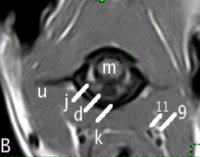

INERVACIÓN SIMPÁTICA DEL OJO: el gran "desconocido": el tronco vagosimpático. |

INERVACIÓN SIMPÁTICA DEL OJO: se indican posibles localizaciones de la lesión en un síndrome de Horner. |